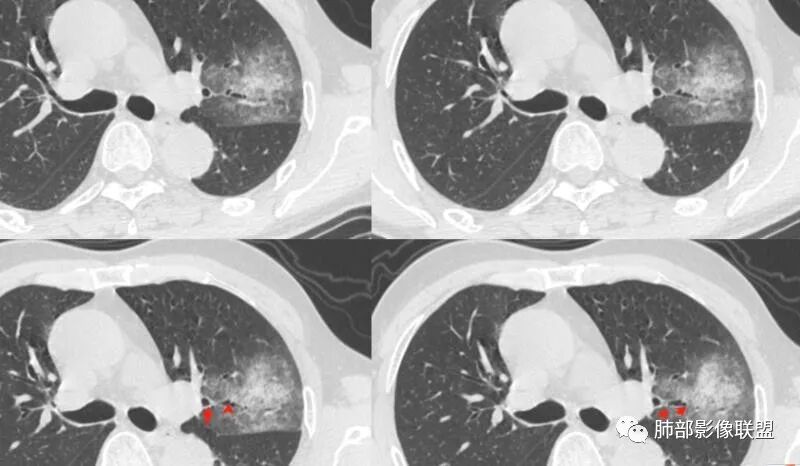

有占位效应吗?

有,斜裂局部膨隆

边缘膨隆,叶间裂有局部膨出下坠

有膨隆+收缩

密度?

实变为主,加周围模糊GGO

GGO+实变

强化如何?

强化有疑问,前面感觉有低密度的,有些图好像又均匀

不均匀中度强化

不均匀轻中度渐进强化。

整体形态

南边:

外围大,内带小

支气管?

支气管外面堵了,近端有扩张

有堵塞,有狭窄

中远端堵塞,堵塞端圆钝

炎性? 肺炎型肺癌待排

血管受侵了吧

空洞内侧软组织肿块,比较支持恶性吧

这个空洞的性质很重要,对最后诊断结果影响大,如果中间没有曲菌球,那就是偏心空洞,指向恶性,如果是曲菌球引起的新月形改变,那就不一定。至于到底是曲菌球还是偏心空洞,需要仔细看看强化情况。

不均匀性强化,远端坏死比较明显

如果强化明确,那就可以排除曲菌球。